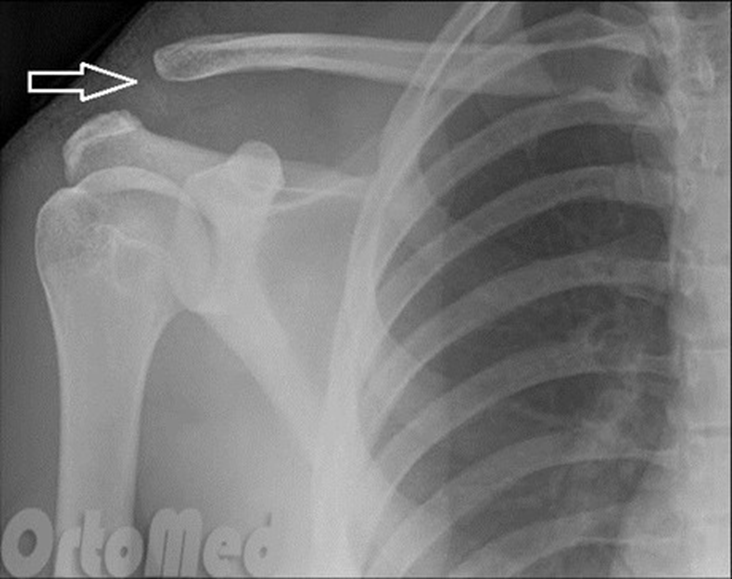

НА ЯКИЙ СУГЛОБ ВКАЗУЄ СТРІЛКА НА РЕНТГЕНОГРАМІ? КІСТКИ ЯКОГО ВІДДІЛУ СКЕЛЕТУ ВІН З'ЄДНУЄ?

варіанти відповідей

ГРУДНИННО-КЛЮЧИЧНИЙ С.

ПЛЕЧОВИЙ С.

НАДПЛЕЧОВО-КЛЮЧИЧНИЙ С.

АКРОМІАЛЬНО-КЛЮЧИЧНИЙ С.

КІСТКИ ВЕРХНЬОЇ КІНЦІВКИ

КІСТКИ ТУЛУБА І ВЕРХНЬОЇ КІНЦІВКИ